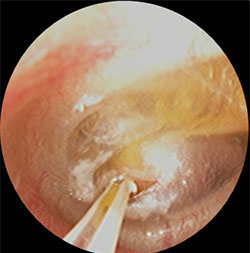

・上記の滲出性中耳炎の鼓膜に小さな切開をいれ、内部の液体を吸引し、鼓膜チューブを挿入

・左図の処置後から1週間後、鼓膜内側には液体は溜まっておらず、正常の鼓膜の色である